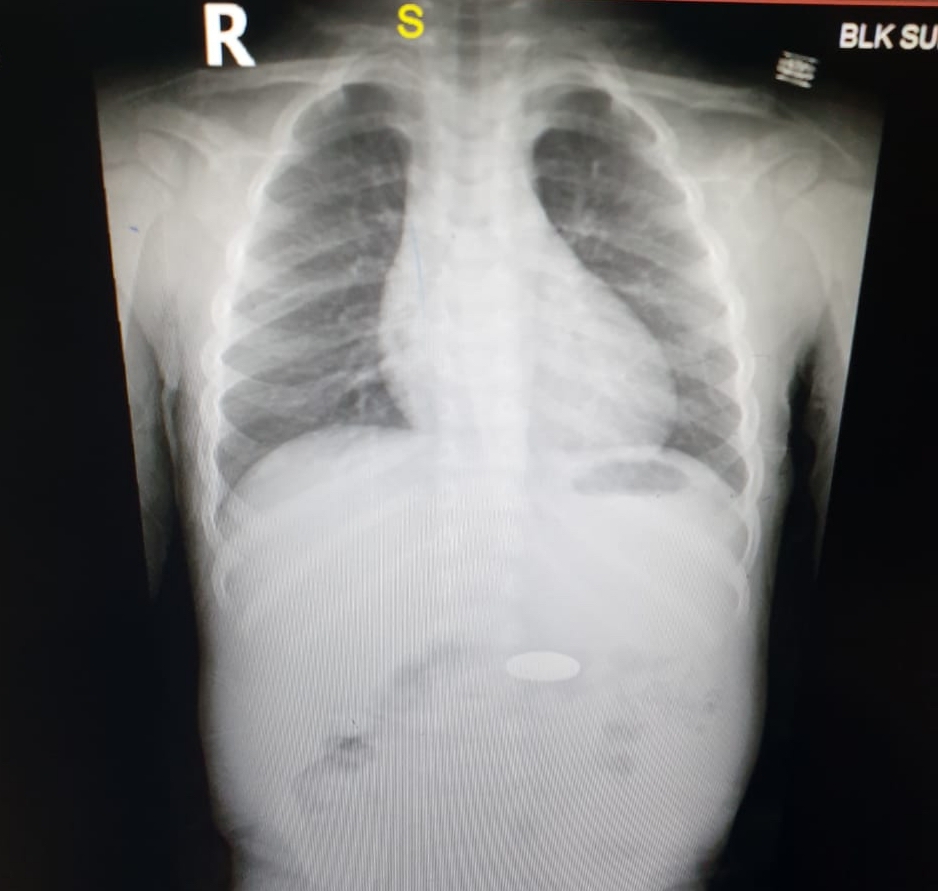

The above case (radiograph above), a 2.5 year old boy had presented with h/o ingestion of disk/button battery from a TV remote, few minutes back. It was retrieved Endoscopically using a Roth net child was discharged to home within 3 hours. There was no surrounding mucosal injury as it was removed timely.